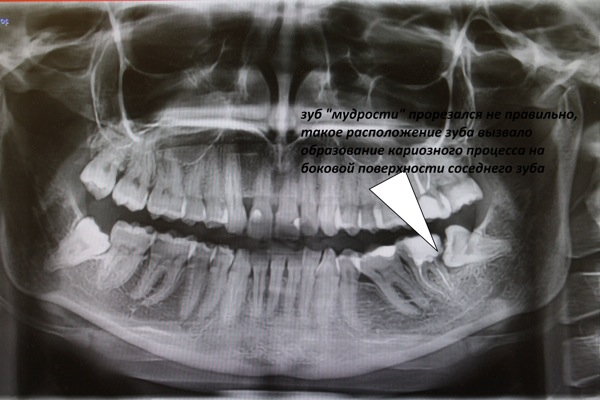

Дентальные снимки и диагностика кариеса